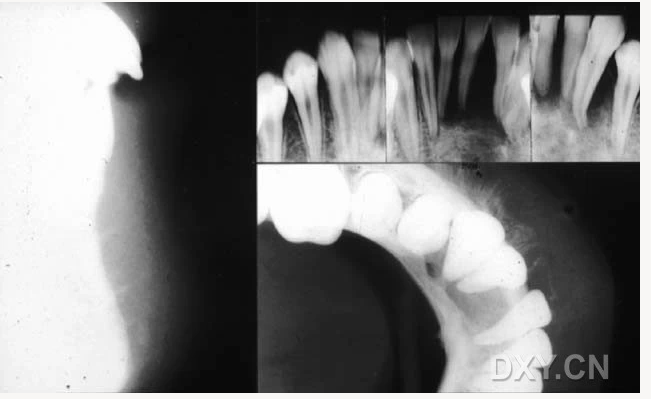

骨髓炎

頜骨骨折